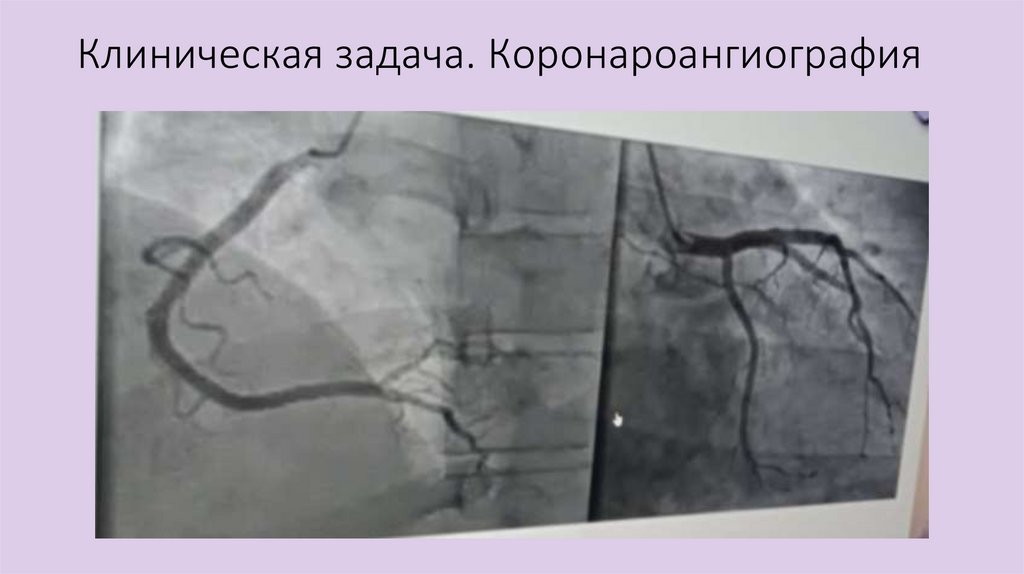

Клиническая задача. Коронароангиография

Клиническая задача. Вопросы

1. Предположите диагноз

2. Назовите основное осложнение

3. Опишите ЭКГ

4. Дополните обследования еще одним важным

упущенным методом

5. Предположите основной метод лечения

Клиническая задача. Ответы

1. Предположите диагноз – Болезнь Леви-Ленегра

2. Назовите основное осложнение – Синдром

Морганьи-Эдэмса-Стокса

3. Опишите ЭКГ – Синусовый ритм. ЭОС влево. ЧСС

60/мин. АВ 2ст М2 (с проведением 2:1), ПБЛНПГ

упущенным методом – ХМ-ЭКГ

5. Предположите основной метод лечения –

имплантация ЭКС